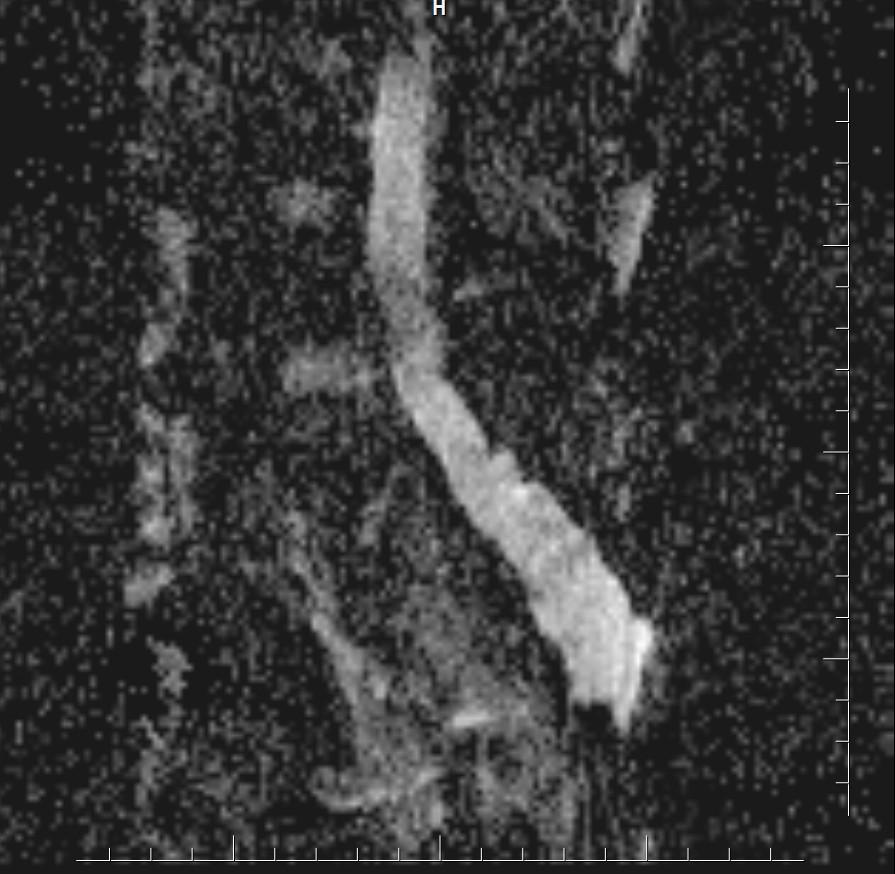

MR images demonstrated large cystic lesion in the sacral canal.

MRI is the best modality to assess an occult intrasacralmeningocele.

• T1: hypointense(isointense to CSF)

• T2: hyperintense (isointense to CSF)

• T1C+ (Gd): no enhancement

• DWI: hypointense, no restricted diffusion